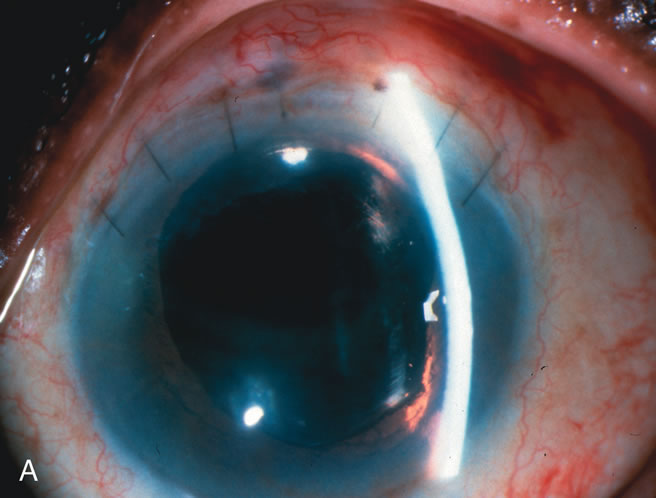

CATARACT EXTRACTION ALONE REDUCES IOP IN MOST EYES WITH ANGLE-CLOSURE GLAUCOMA

Uncomplicated cataract extraction substantially reduces IOP, along with the number of postoperative glaucoma medications in eyes with angle-closure glaucoma.146,147 When preoperative gonioscopy reveals PAS, along with adjacent areas of appositional closure, lens extraction alone in select cases may be a reasonable alternative to filtration surgery.148,149 Phacomorphic angle-closure disease due to enlargement of the lens with progressive angle crowding is eliminated following lens extraction. The width and depth of the anterior chamber angle in eyes with angle-closure glaucoma increases significantly after cataract extraction with IOL implantation and becomes similar to open-angle glaucoma and normal eyes.150,151 (Fig. 5). Combining phacoemulsification, IOL implantation, and limited goniosynechialysis is effective in the treatment of cataract and chronic angle-closure glaucoma.152 Phacoemulsification with implantation of a foldable IOL is more effective in reducing IOP and improving visual acuity than surgical peripheral iridectomy in eyes with acute angle-closure glaucoma.153

Fig. 5. Anterior chamber angle changes associated with lens extraction and PCIOL This 65-year-old Vietnamese woman has a long-standing history of chronic angle-closure glaucoma treated with laser peripheral iridectomy. The optic nerve demonstrated mild glaucomatous damage and IOP was moderately controlled on two antiglaucoma medications. The cataract was removed through temporal clear corneal phacoemulsification with foldable acrylic IOL. A. Symptomatic cataract in narrow-angle glaucoma eye with patent iridectomy. B. Intraoperative goniophotograph showing crowding of angle with increasing narrowness due to phacomorphic component. C. Intraoperative photograph showing temporal clear corneal approach with IOL in the capsular bag. D. Intraoperative goniophotograph demonstrating deepening of chamber angle following lens extraction. Proposed theories for IOP reduction following lens extraction with complete wound closure: